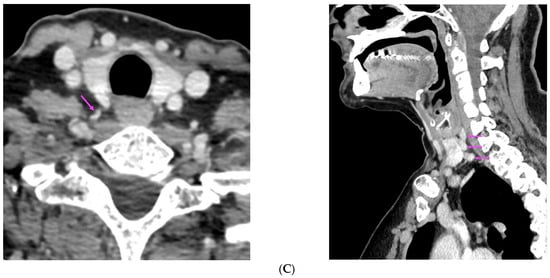

We report a case of 16-year-old female primary hyperparathyroidism patient who underwent cervical ultrasonography and 99mTc-sestamibi single photon emission computed tomography/computed tomography, both of which were negative for parathyroid adenoma. Subsequent 11C-methionine positron emission tomography/CT showed positive focal uptake suggesting parathyroid [...] Read more.

We report a case of 16-year-old female primary hyperparathyroidism patient who underwent cervical ultrasonography and 99mTc-sestamibi single photon emission computed tomography/computed tomography, both of which were negative for parathyroid adenoma. Subsequent 11C-methionine positron emission tomography/CT showed positive focal uptake suggesting parathyroid adenoma, which then was confirmed pathologically. Full article